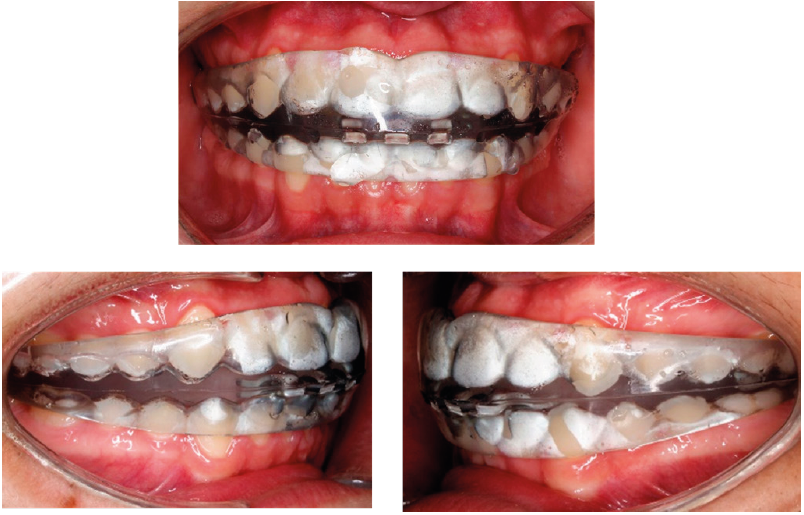

El tratamiento de elección constó de dos fases: una ortopédica y posteriormente la ortodóncica. Inició con la colocación de tornillo Hyrax de 7 mm (Figura 4. A) con máscara facial reversa y elásticos de 12oz iniciales. Se utilizó máscara facial reversa durante 10 meses aumentando la fuerza gradualmente (Figura 4. B-C). Posteriormente se realizaron microosteoperforaciones (MOP´s) en 3 ocasiones en la zona subapical (fondo de saco) entre los dientes 13 al 23 con miniimplantes de 2mm x 10mm de acero inoxidable, en intervalos de 8 semanas, para estimular las suturas intermaxilares y favorecer la tracción maxilar.

Figura 4 Fase ortopédica. A. Colocación de Hyrax cementado con bandas. B. Fotografía extraoral lateral con la colocación de máscara facial reversa. C. Fotografía extraoral lateral de avance, 10 meses de uso de la máscara facial reversa.